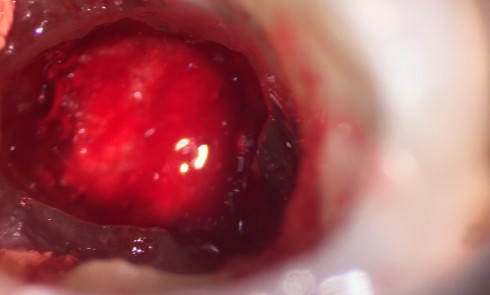

Partie 4 – Gestion des complications endodontiques Traitement des résorptions La majorité des résorptions inflammatoires sont des complications survenant à...